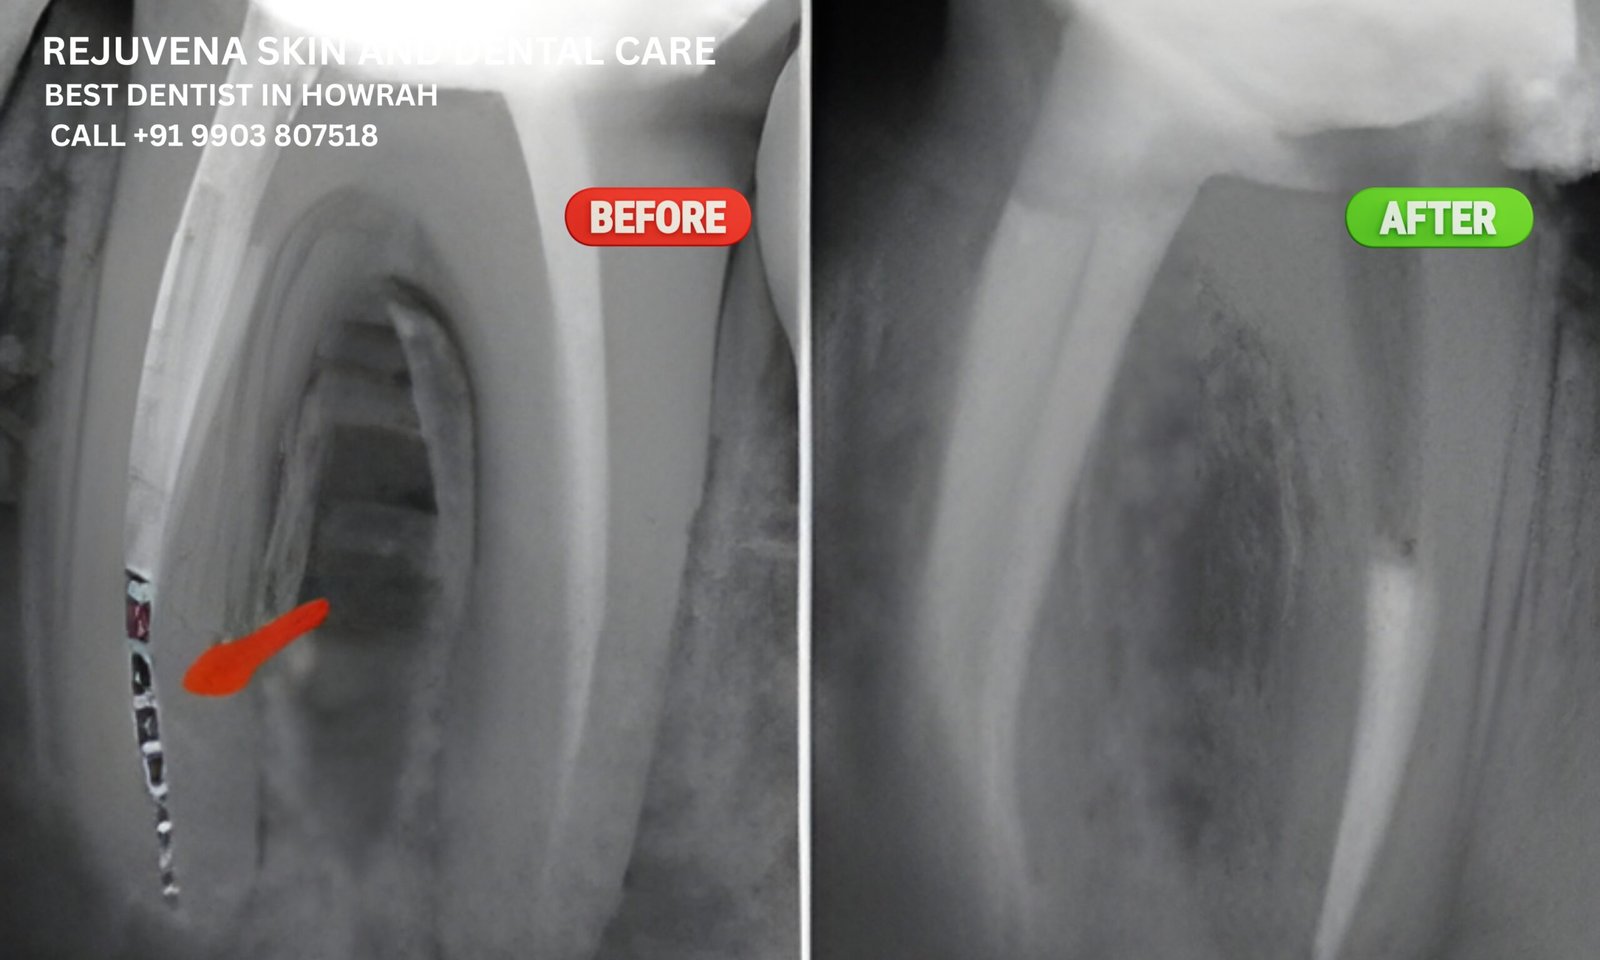

In rare cases during root canal treatment, a dental instrument may break inside the canal. At Rejuvena, we use magnification and ultrasonic tools to retrieve these broken instruments safely without damaging the tooth. Our RCT specialists in Howrah have the training and technology to manage such complications efficiently. For patients needing instrument retrieval near B Garden, Rejuvena is among the few clinics equipped to handle this advanced endodontic challenge.